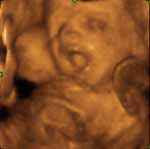

ECOGRAFIA 3D ÀS 10 SEMANAS DE GESTAÇÃO

Uma das questões mais discutidas no debate do referendo do aborto é a questão da vida de um feto com 10 semanas.

Será um feto com 10 semanas uma vida humana?

Sim, é! Sem dúvida que é!

Um feto com 10 semanas é um ser humano!

Um feto com 10 semanas possui o seu próprio código genético, que torna este novo ser diferente de todos os outros seres humanos que viveram no passado, vivem no presente e viverão no futuro!

Mas como uma imagem vale mais do que mil palavras, sugiro a todos (aos que ainda têm dúvidas e aos que já não têm) que visitem o site http://www.medicosporissonao.com/

Trata-se do site do movimento "Somos médicos, por isso Não", onde se encontram inúmeros videos sobre a vida intra-uterina, ecografias 2D e 3D às 10 semanas e muitas fotografias que não deixam qualquer dúvida:

a vida humana começa na concepção!

um feto com 10 semanas é uma vida humana!

Às dez semanas está completo um quarto da vida intra-uterina, iniciada na concepção com o zigoto que resultou da união do espermatozóide e do óvulo. O então denominado feto, com um código genético único, já possui todos os órgãos e sistemas corporais, que se encontram em crescimento e diferenciação aceleradas. O sistema nervoso central, que se vai desenvolver durante toda a vida, surgiu às três semanas, já apresenta os hemisférios com córtex (substância cinzenta) e tem actividade cerebral, que se regista em traçados electroencefalográficos. Verificam-se movimentos espontâneos dos braços e pernas, possuindo músculos e dedos, com unhas e impressões digitais. Os olhos têm pálpebras, íris e córnea, a boca tem língua e engole líquido amniótico. Surgiram os primeiros folículos capilares, de onde em breve nascerá cabelo. Os rins já produzem urina. Estão diferenciados os órgãos sexuais masculinos e femininos. O coração está formado, assemelha-se ao do adulto e cumpre a sua função circulatória, que assegura o crescimento do feto, com uma frequência cardíaca média de cerca de 175 pulsações por minuto.

Às dez semanas existe um ser humano complexo e em desenvolvimento até ao nascimento.